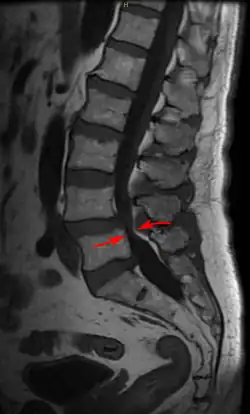

| Lumbar vertebra showing central stenosis and lateral recess stenosis. | |